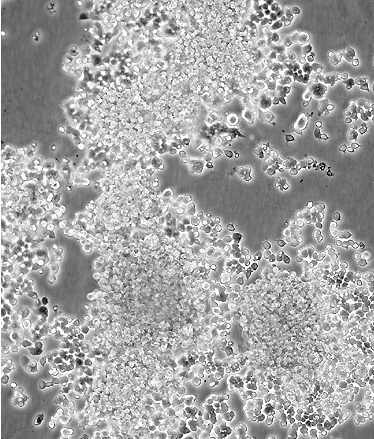

PC-12(高分化)

中文名稱 大鼠腎上腺嗜鉻細胞瘤細胞(高分化)

生長特性 adherent

形態(tài)特征 polygonal

細胞描述 該細胞系來自能移植的雄性大鼠腎上腺嗜鉻細胞瘤。這些細胞表達神經生長因子(NGF)受體。NGF可誘導產生神經表型。這些細胞不合成腎上腺素。